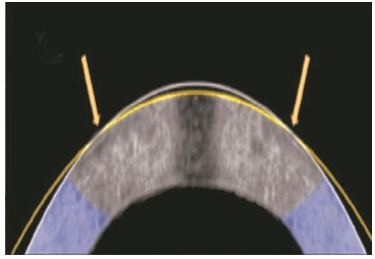

“电—机械重塑”方法将兔子角膜(横截面图)从原来的形状(白线)矫正为新的形状(黄线)。

图片来源:美国加州大学尔湾分校